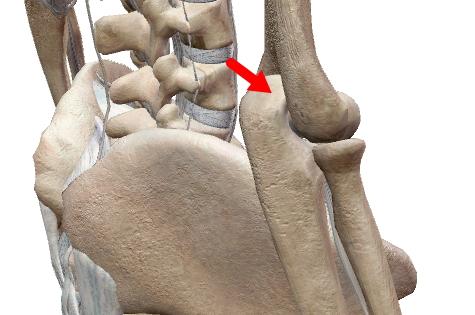

線維性軟骨結合は、幼児期の寛骨(腸骨・恥骨・坐骨)、恥骨結合。

結合以外に【関節円板】と呼ばれるものは全て(椎間板、半月板、顎関節・胸鎖関節・手関節の関節円盤)は線維性軟骨です。

関節円板は骨化するとは限りませんが(する場合もあり)、線維性軟骨結合はやはり加齢とともに骨化します。